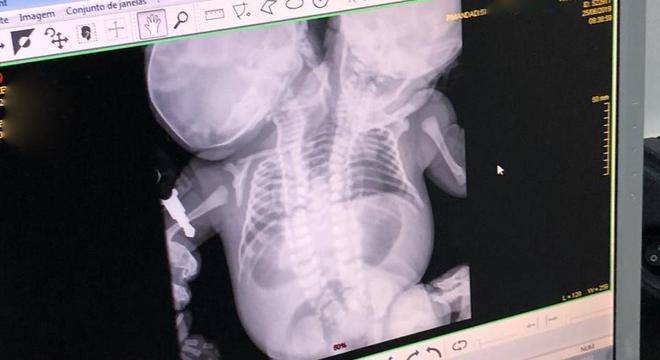

Após descobrir uma gestação de gêmeas siamesas toracópagas, com cardiopatia complexa, pois as duas tem apenas um coração, onde a viabilidade de vida extrauterina é quase nula, levou uma moradora da cidade a recorrer à Justiça para interromper a gravidez, que inclusive poderia colocar sua vida em risco.

Casos como este são raríssimos. Dados médicos indicam que gêmeos siameses toracópagos ocorrem em cerca de um nascimento a cada 250 mil. Ainda assim, o número corresponde apenas a casos de nascidos vivos, sem incluir situações de inviabilidade total como a registrada em Prudente.

Os pareceres ressaltaram que os fetos eram unidos pelo tronco e compartilhavam um único coração com cardiopatia grave, quadro apontado pela literatura médica como absolutamente incompatível com vida extrauterina. Assim, a interrupção não configuraria crime e seria necessária para resguardar a saúde física e mental da gestante.